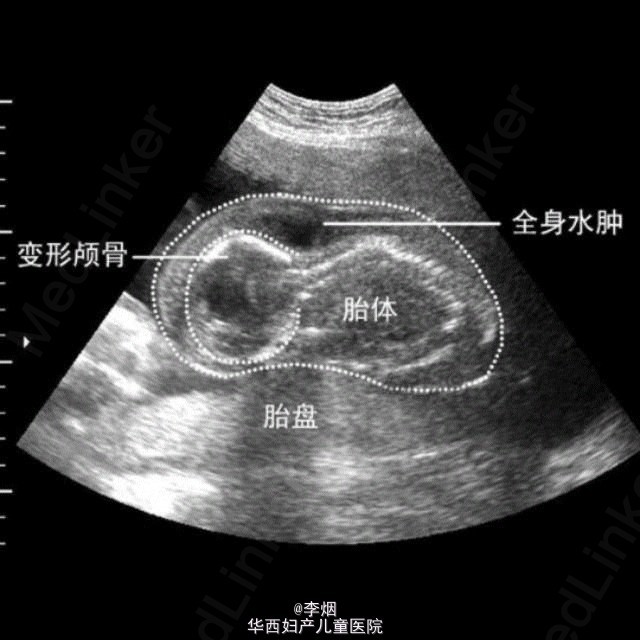

死胎

胎儿无胎心搏动,无胎体胎肢的活动,肌张力消失。 来自中山大学网络课程